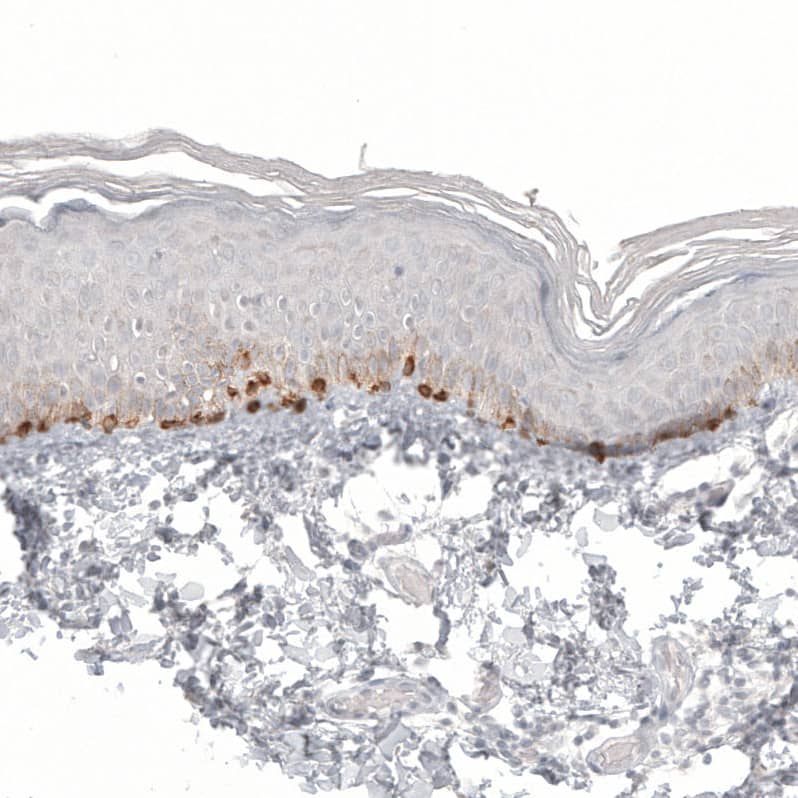

Staining of human skin shows strong cytoplasmic positivity in melanocytes.